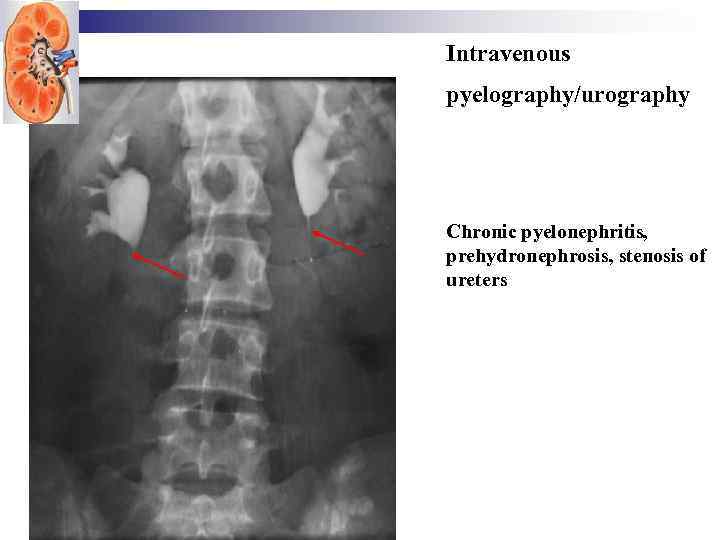

Intravenous pyelography/urography

Intravenous pyelography/urography

Intravenous pyelography/urography Chronic pyelonephritis, prehydronephrosis, stenosis of ureters

Intravenous pyelography/urography Chronic pyelonephritis, prehydronephrosis, stenosis of ureters